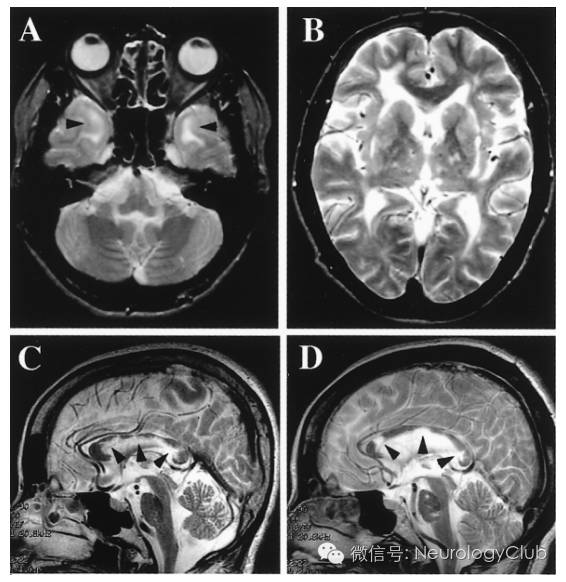

CADASIL患者在临床症状出现前即可有影像学上的改变。多对称分布,在MRI的T2像表现为大小不一的高信号,不累及弓状纤维。主要位于侧脑室周围和深部白质。以额叶白质最常受累,其次为颞叶和顶叶,而枕叶受损程度相对较轻。其中,外囊、颞极的对称性异常信号对诊断有高度提示作用。胼胝体亦可全层受累,引起胼胝体萎缩。皮层一般不受累。

疾病早期出现血管周围间隙加大,继而出现对称性孤立的单个结节状高信号区,此阶段容易与多发性硬化混淆。这些白质异常信号可以进一步扩大表现为外囊和颞极的高信号,对于年龄在20-30岁的亚临床患者,其颞极白质以及侧脑室周围出现帽状异常信号是其最早期的改变。随着病程进展双侧半球白质内大片长T2信号区相互融合,晚期小脑和脑干也受累及,约半数患者出现脑干长T2信号,其中脑桥(100%)比中脑(68%)和延髓(35%)更易受累,这一现象与年龄增长相关,出现双侧脑干病灶的CDADASIL患者可能预后不良。

颞极白质T2/FLAIR呈高信号是CADASIL的特征性表现,也称为O’Sullivan征,在 皮质下动脉硬化性脑病中无此现象,对本病的诊断敏感度为89%,特异度为86%。但O’Sullivan征对中国人CADASIL诊断并不是敏感指标。

外囊受累是CADASIL的另一特异征象,表现为T2/FLAIR高信号,诊断CADASIL的敏感度和特异度分别为93%和45%,并有助于CADASIL与其他小动脉疾病的鉴别诊断。本病也可累及基底节区内囊前肢额桥束,如外囊钩状纤维束和内囊前肢同时受累,在T2/FLAIR横轴位图像高信号呈“人”字征(Herringbone pattern)。

2腔隙性脑梗死

可广泛存在于大脑皮层下白质、基底节、丘脑、外囊、胼胝体和脑干等部位。腔隙性脑梗死在基底节的出现率高达100%,但出现在胼胝体和外囊等特殊部位的梗死灶更具有诊断价值。

(图3:T2WI可见CADASIL特征性的颞极高信号和外囊受累)

(图4:MRI上可见颞极、脑室旁和深部白质病变)

(图5:A:T1WI可见脑室旁低信号病灶;B-C:FLAIR可见脑室旁高信号病灶,外囊受累,基底节区可见腔隙性梗死)

(图9:A:颞极高信号病变;B:皮质下、外囊高信号病变;C-D:两例患者均有胼胝体受累[箭头])